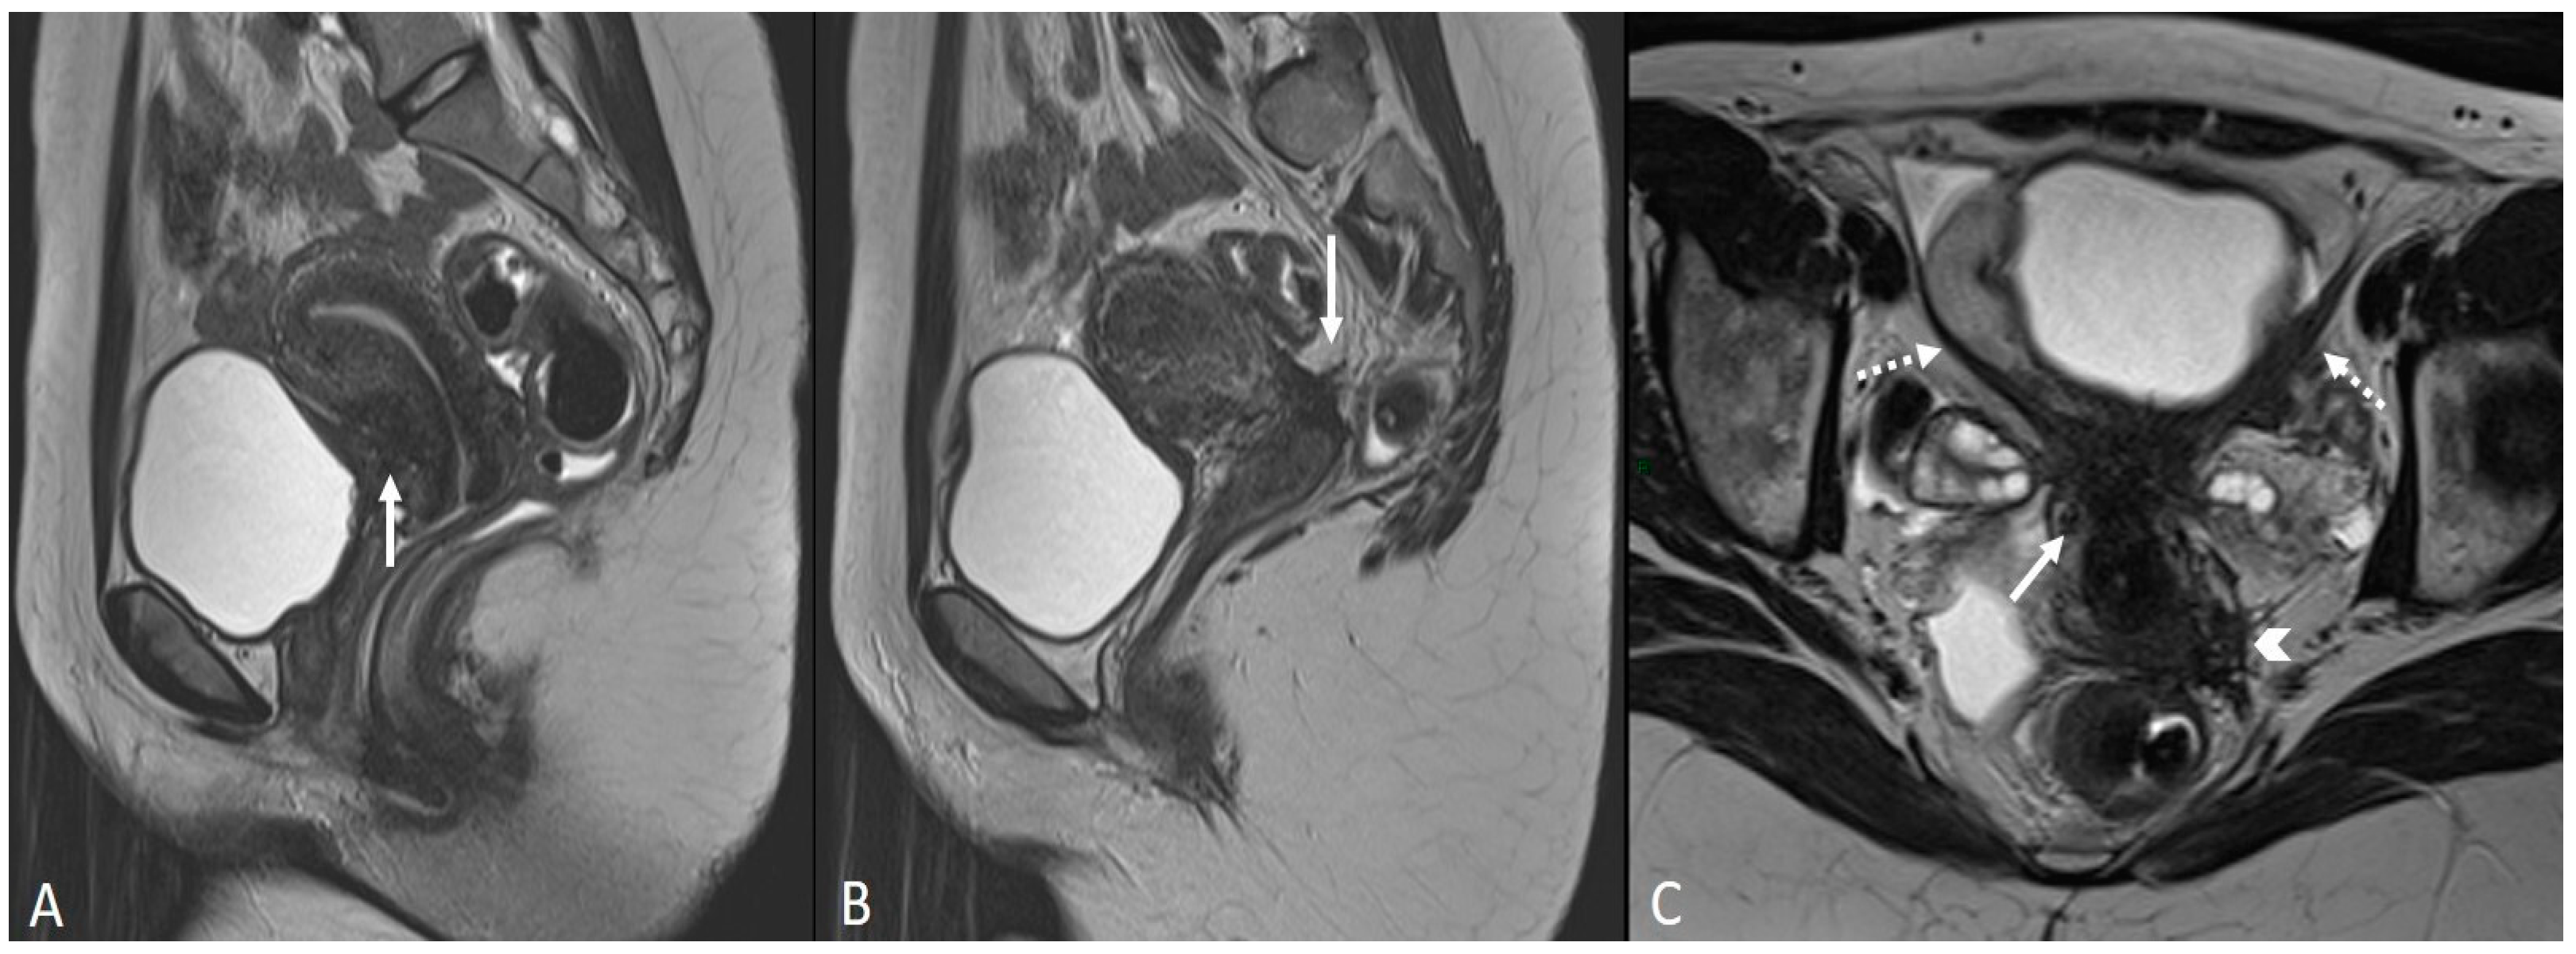

3.2.5. Rectosigmoid Colon

- Rousset, P.; Florin, M.; Bharwani, N.; Touboul, C.; Monroc, M.; Golfier, F.; Nougaret, S.; Thomassin-Naggara, I.; ENDOVALIRM Group. Deep Pelvic Infiltrating Endometriosis: MRI Consensus Lexicon and Compartment-Based Approach from the ENDOVALIRM Group. Diagn. Interv. Imaging 2023, 104, 95–112. [Google Scholar] [CrossRef]

- Bazot, M.; Kermarrec, E.; Bendifallah, S.; Daraï, E. MRI of Intestinal Endometriosis. Best Pract. Res. Clin. Obstet. Gynaecol. 2021, 71, 51–63. [Google Scholar] [CrossRef] [PubMed]

- Tang, X.; Ling, R.; Gong, J.; Mei, D.; Luo, Y.; Li, M.; Xu, J.; Ma, L. Deep Infiltrating Endometriosis MR Imaging with Surgical Correlation. Quant. Imaging Med. Surg. 2018, 8, 187–195. [Google Scholar] [CrossRef] [PubMed]